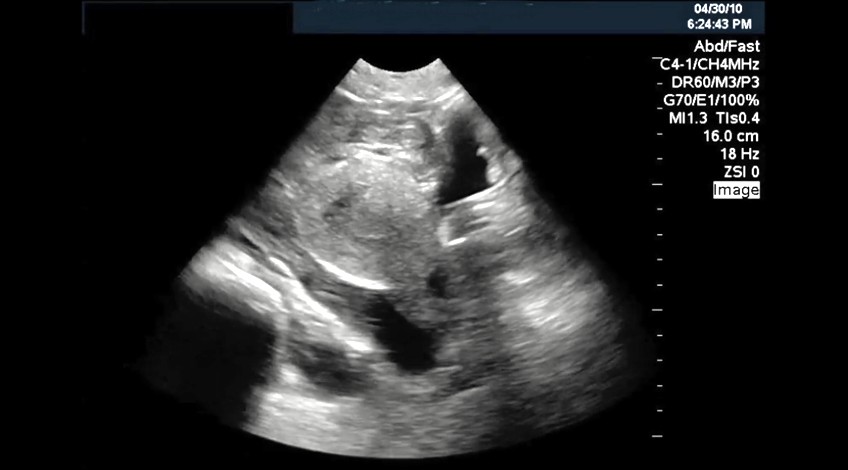

Ecotomografía Pelviana

- ¿Qué es? Examen que se realiza para estudiar el útero, ovarios y vejiga tanto en niñas como en niños.

- Preparación Se requiere que el paciente acuda con la vejiga en repleción por lo que le sugerimos beber abundante líquido desde un par de horas antes del examen y no orinar hasta que se lo indiquen.